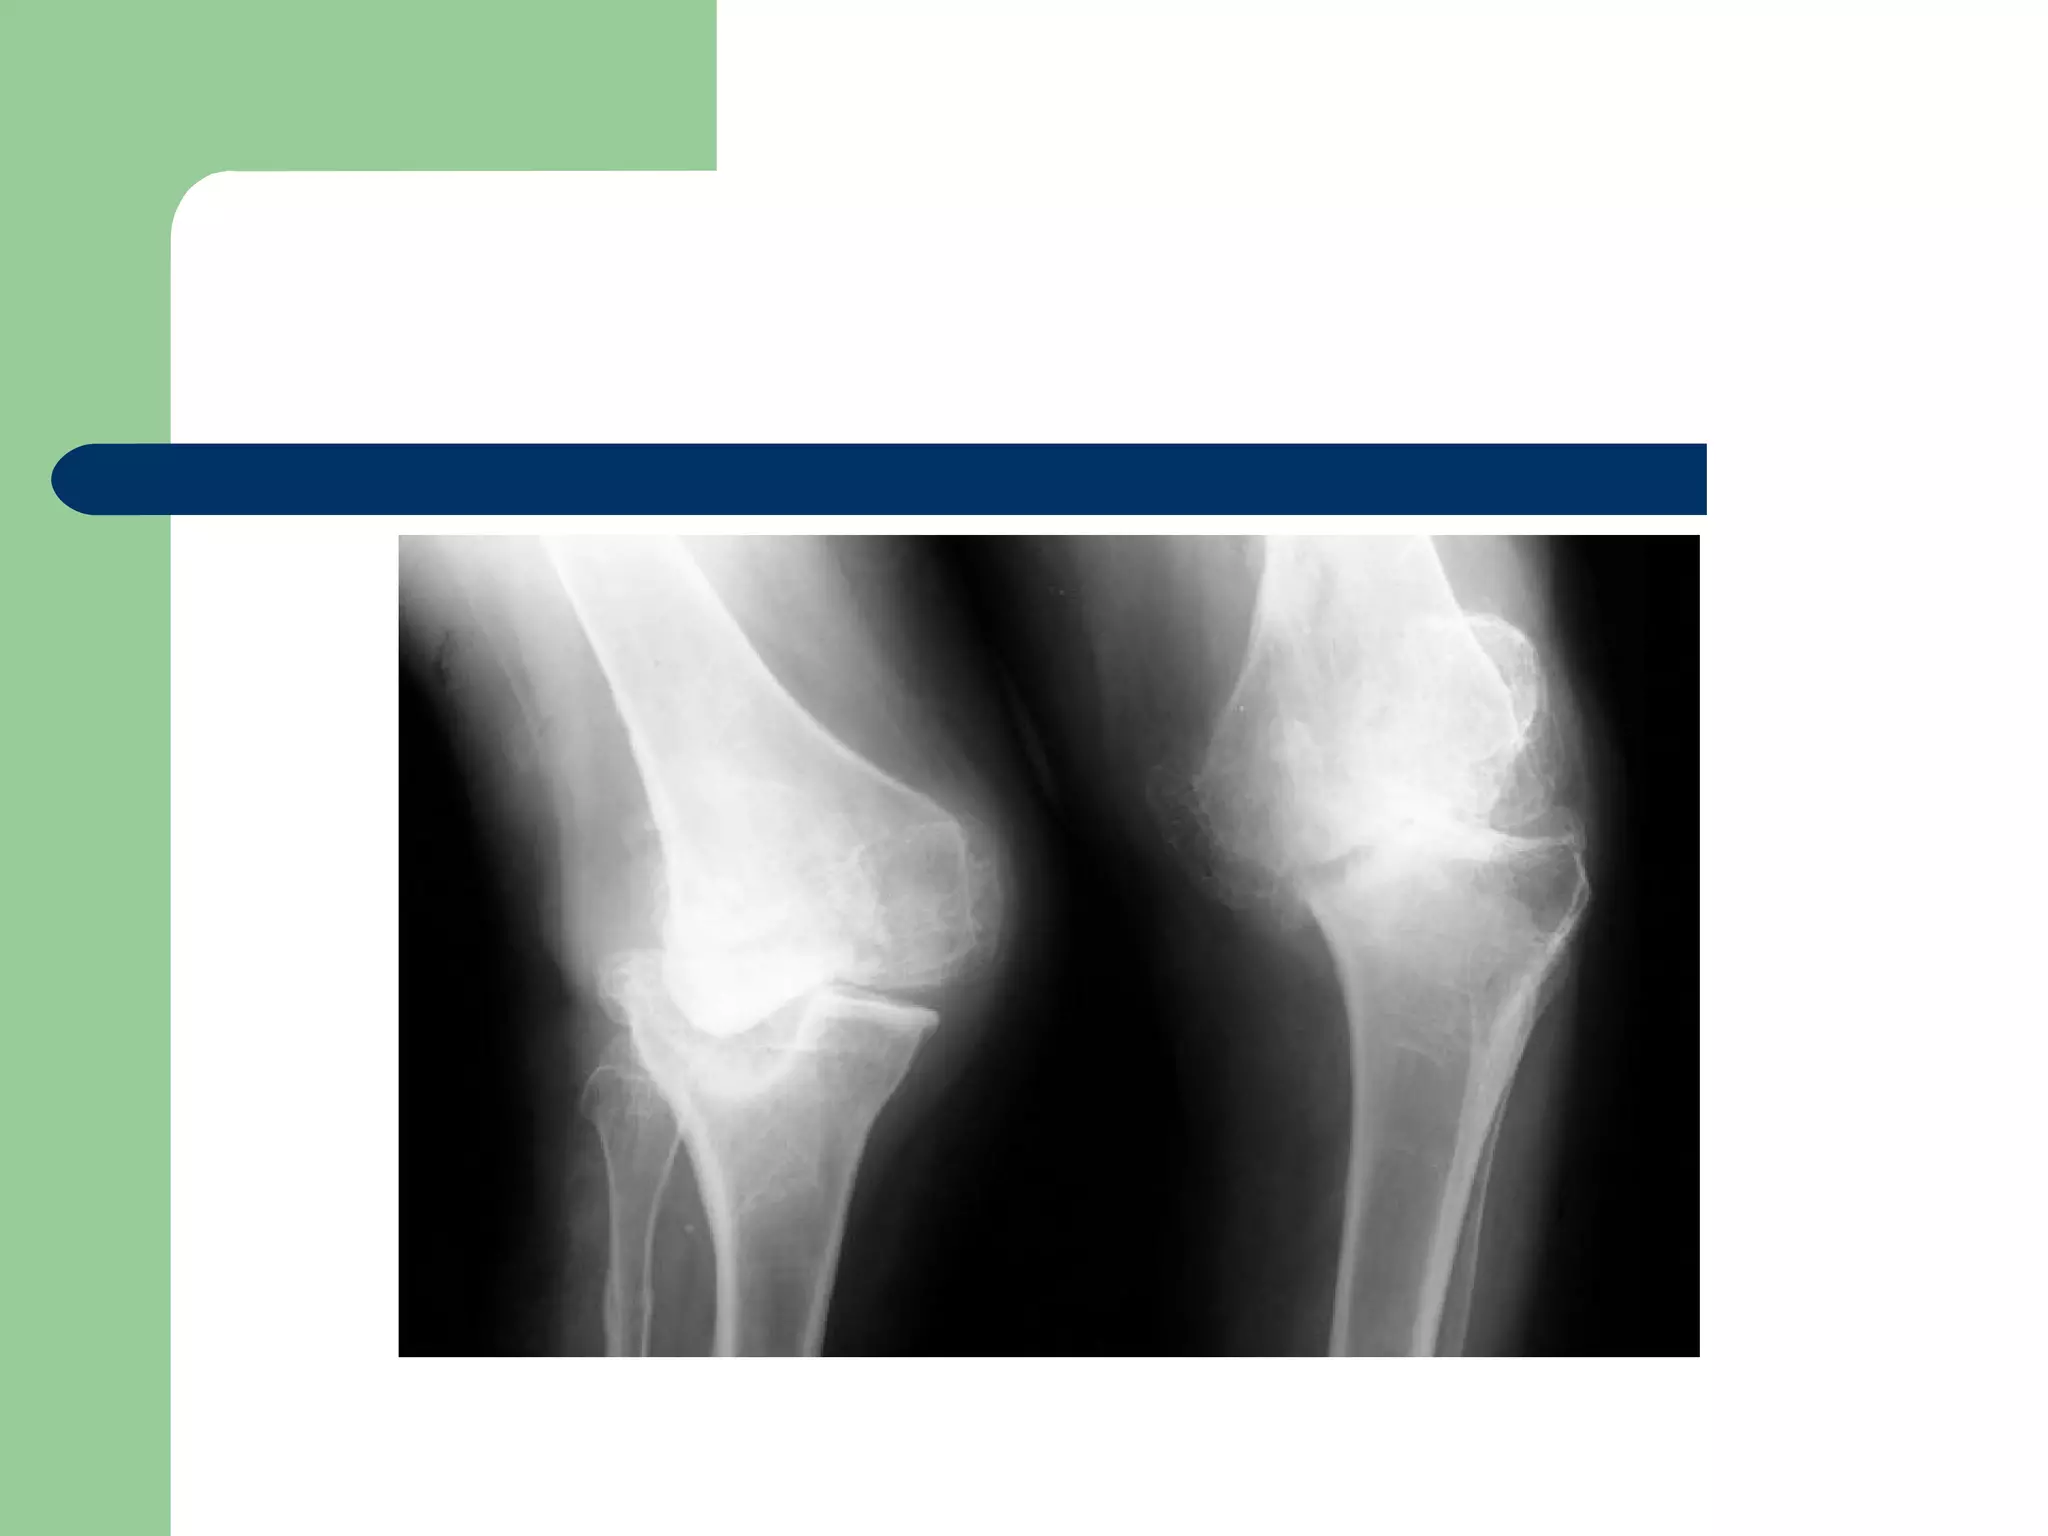

KNEE

 Most Commonly secondary to Syphilis.

 Results in Gross Instability

 If only one knee is involved and destruction

is severe, fusion is indicated.

 Total knee arthroplasty ???

KNEE  Most Commonlysecondary to Syphilis.  Results in Gross Instability  If only one knee is involved and destruction is severe, fusion is indicated.  Total knee arthroplasty ???